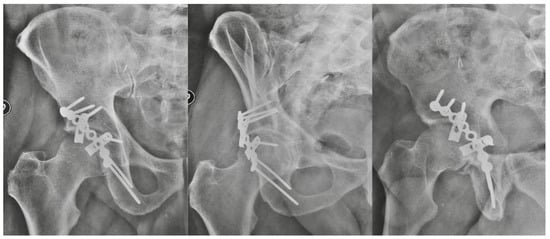

Spring Plates as a Valid Additional Fixation in Comminuted Posterior Wall Acetabular Fractures: A Retrospective Multicenter Study

2. Materials and Methods

3. Results